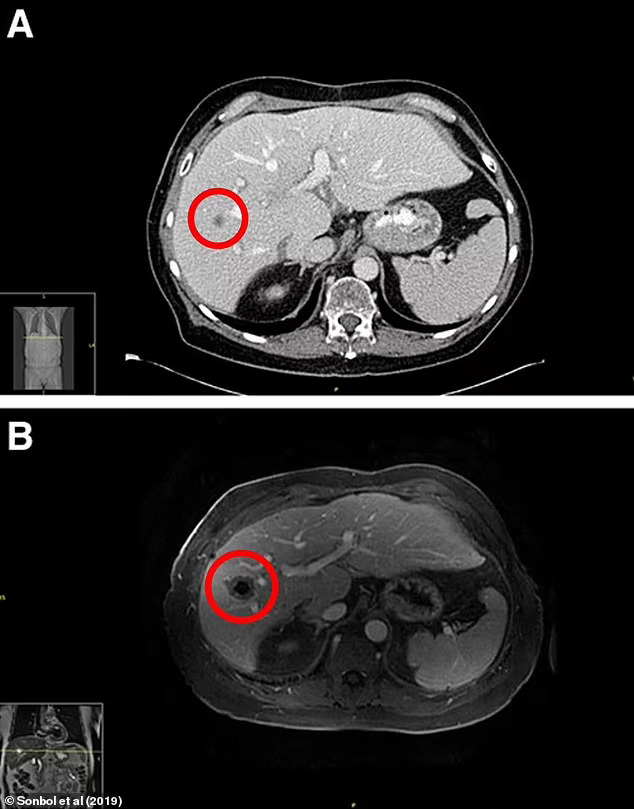

美國一名69歲男性因長期酗酒導致肝硬化,原本順利完成肝臟移植手術,以為能重獲新生,沒想到術後僅4個月,就在例行超音波檢查中被發現肝臟冒出兩顆來路不明的腫塊。更令人震驚的是,6週後又陸續出現多處新生腫瘤,數量多到難以精確計算,最終確診為高度侵略性的「轉移性肺癌」。

根據《每日郵報》報導,由於癌細胞已從原發位置大範圍擴散至全身各處,男子已失去再次接受肝臟移植的機會,同時必須停用抑制免疫排斥的藥物。儘管經過數月積極治療,癌細胞仍持續蔓延,男子最終不幸離世。透過PCR基因檢測結果顯示,這些癌細胞的特徵與男子原有的肝癌完全不同,證實捐贈者本身患有未被診斷出的晚期肺癌,且已轉移到肝臟。